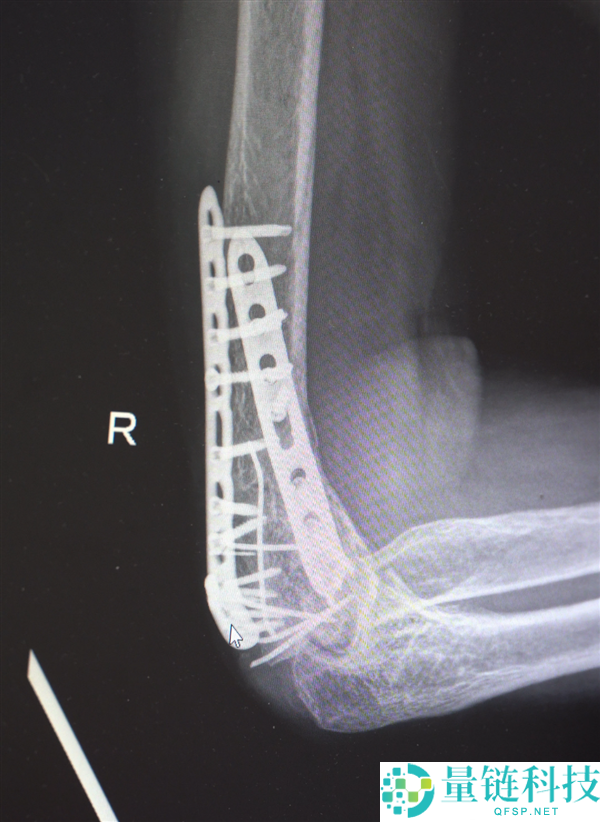

鉴于男子多处骨折,其中最严重的当属右肘部C3型粉碎性骨折,关节面及髁上严重粉碎(碎成了七块),肘关节易粘连,复位固定难度极高。

最终医疗团队采用了“拼古董”式复位固定技术,就像修复一件珍贵的古董瓷器,先拼接大块骨块再贴合小块,先后进行了两次手术。

部分手术后拍摄的影像